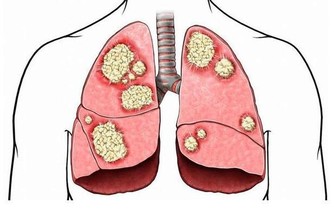

環境中的污染氣體吸收到了身體裡沒有排出去,這些一點點累積,就成了身體毒素。